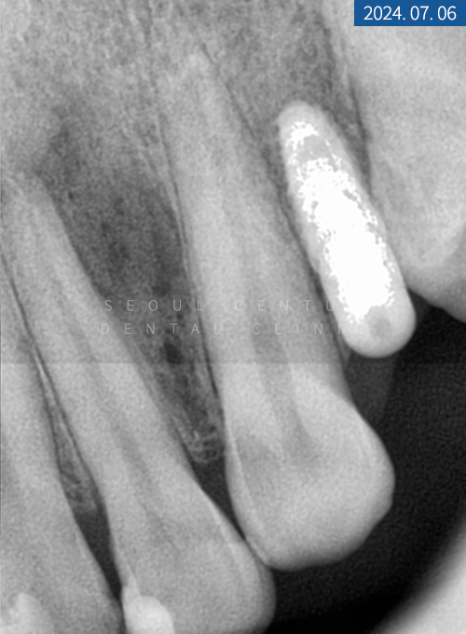

이번에 찾아오신 20대 환자분의 상태를 정확히 파악하기 위해 파노라마 엑스레이 촬영을 해보니 위턱과 아래턱 영구치 상실이 여러 군데 보였고 상악 전치부 부분 크랙이 심했습니다. 연령이 낮아 큰 골 소실은 없었지만 우측 상악 제1 소구치는 하방에 염증이 생겨 픽스처를 심는다면 GBR이 필요했는데요.

크랙도 범주가 크고 깊어 그대로 놔두게 되면 치수 감염과 하방 파절이 우려되어 조속한 대처가 필요했습니다.

진단

상실된 #14번은 합성골을 이식한 후 네이바이오텍 픽스처 직경 4.5mm, 높이 10mm로 이식하기로 했고 당일 좌측 상악 #15번 소구치도 동일한 브래드의 픽스처 4.0mm x 8.5mm 크기로 심기로 했습니다. 크랙이 심한 앞니와 측절치는 보철물을 수복해서 영구치를 보존하기로 했으며 크라운보다 치아 삭제량이 적고 심미적인 라미네이트를 부착하기로 했습니다.